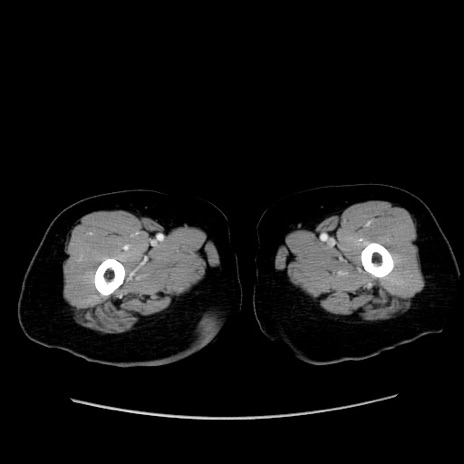

症例19(横断像)

【症例】80歳代女性

【主訴】下腹部痛

【現病歴】約8時間前より下腹部痛の出現あり、救急外来受診。

【既往歴】両側付属器切除

【身体所見】意識清明、下腹部正中に手術痕あり、その部位に一致して圧痛と反跳痛あり。腸蠕動音は亢進。

【データ】WBC 9300、CRP 0.15